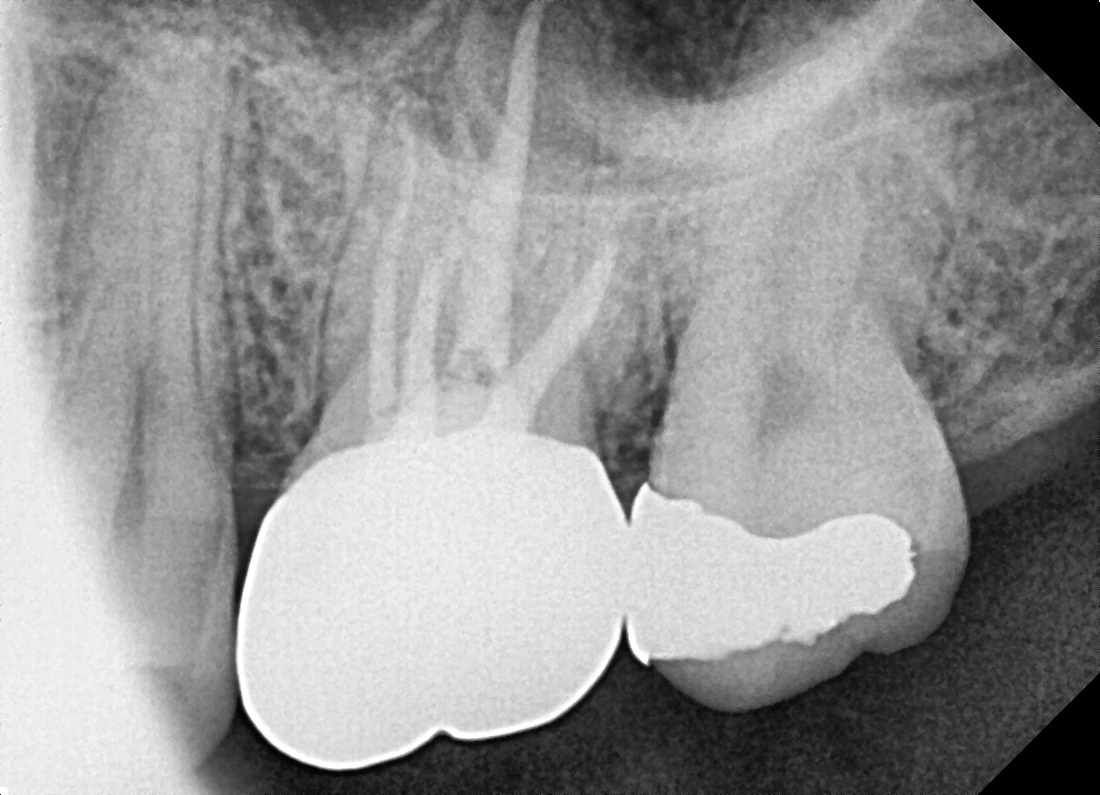

치근단병소 치유

심한 염증으로 고름이 찬 어금니

Before

After

치료 6개월 후 치근단병소 완전 치유